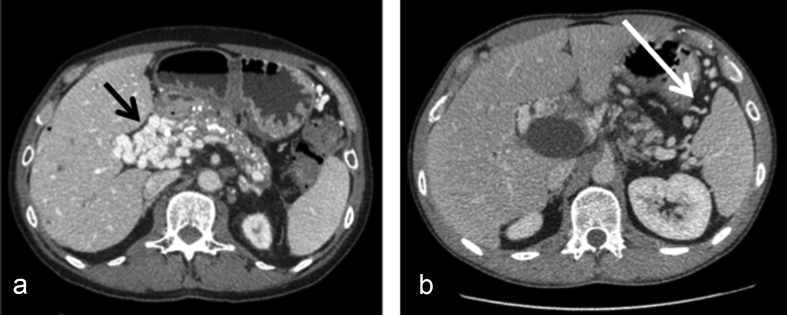

Radiological findings are summarized in Table 1. In non cholecystectomized patients (26/30), radiological evaluation showed constant (26/26) perivesicular collateral venous circulation. All patients with biliary obstruction (n = 14) underwent a preoperative biliary evaluation by endoscopic retrograde cholangiopancreaticogram (n = 13) and magnetic resonance imaging (n = 14) and all except one had undergone endoscopic (n = 13) or percutaneous (n = 2) biliary stenting between 1 and 4 years before. In patients with chronic pancreatitis (n = 12), biliary obstruction was mainly related to the underlying disease and located in the intrapancreatic portion of the main bile duct and mildly affected by portal cholangiopathy (Fig. 2A–D). In patients with hematologic disease (n = 2), biliary obstruction was related to main bile duct stenosis (n = 2) with or without stones (1) with mild portal cholangiopathy at the biliary confluence (Fig. 2E–F).

Figure 2.

CT scan (A) of a patient with chronic pancreatitis and portal cavernoma and who presented with recurrent cholangitis. Endoscopic retrograde cholangiopancreaticogram (B) and lateral view of CT scan (C, D) showed distal bile duct obstruction related to chronic pancreatitis with no or mild portal cholangiopathy (black arrow). CT scan (E) in a patient with portal cavernoma related to hematological disease. Magnetic resonance imaging (F) showed stenosis on the main bile duct (white arrow) with associated stones